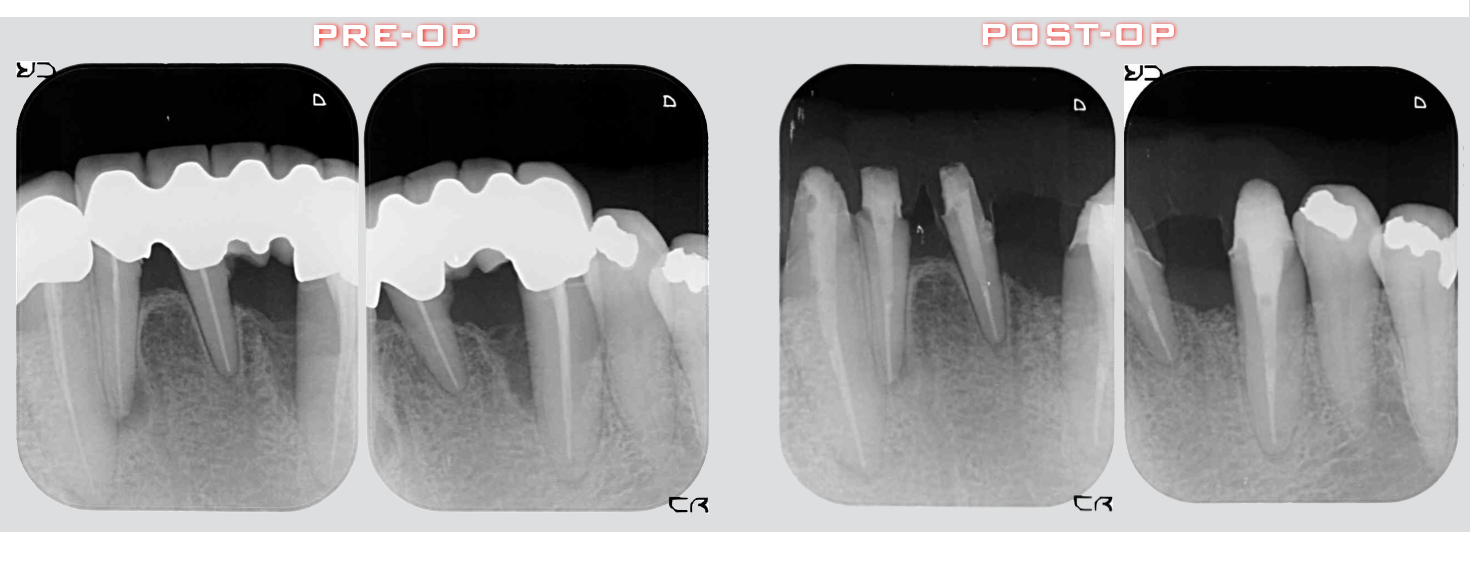

術前術後のレントゲン評価です。よ〜くみてください、違いがおわかりになりますか?